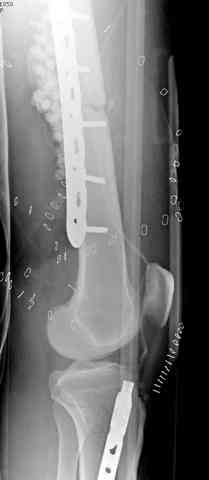

Огнестрельный дефект костей и передней группы мышц, поступил с юнилатеральным аппаратом, стабильность плохая, из раны обильное гнойное

отделяемое. #1;#2. Стержневой апп. снят, наложен апп. Илизарова, дренажно-ирригационная система промывки раны. #3; #4. После стихания инфекции,

аппаратом постепенно создана рекурвация для сближения контактов мышц (сухожилий) передней группы голени. #5;#6. Наложен шов на сухожлилия М.

Tibialis anterior и M extensor digitorum L. Одновременно компактотомия костей голени в В/3 для замешение дефекта костей. #7;#8. Постепенно

исправлена ось и возмещен дефект. В результате восстановление тыльной флекcии стопы и функции конечности. #9;#10;#11

После пары Irrigation& Debridment с вакуумом можно провести окончательную фиксацию интрамедуллярным методом. Чем быстрее, тем лучше, потому что сроки нахождения наружных фиксаторов на конечности тоже имеют значение, риск осложнения увеличивается после длительного пребывания наружного фиксатора.

Открытые переломы, если имеется хороший доступ из раны можно сопоставить и зафиксировать первично пластиной, потому что несопоставленные переломы намного труднее репонируется в поздние сроки. Активизация больного за счет стабилизации кости благоприятно влияет на сращение, а также облегчается манипуляция по закрытию дефекта.

Необходимо доказать проникновение инфекции в кость, иначе агрессивные сегментарные остеотомии кости удлиняет процесс восстановления.

Показания к применению мышечно-ротационной пластики на голени являются обнаженный фрагмент кости, мышца, прикрывая кость восстанавливает питание, а снаружи мышца служит ложем для кожной пластики.